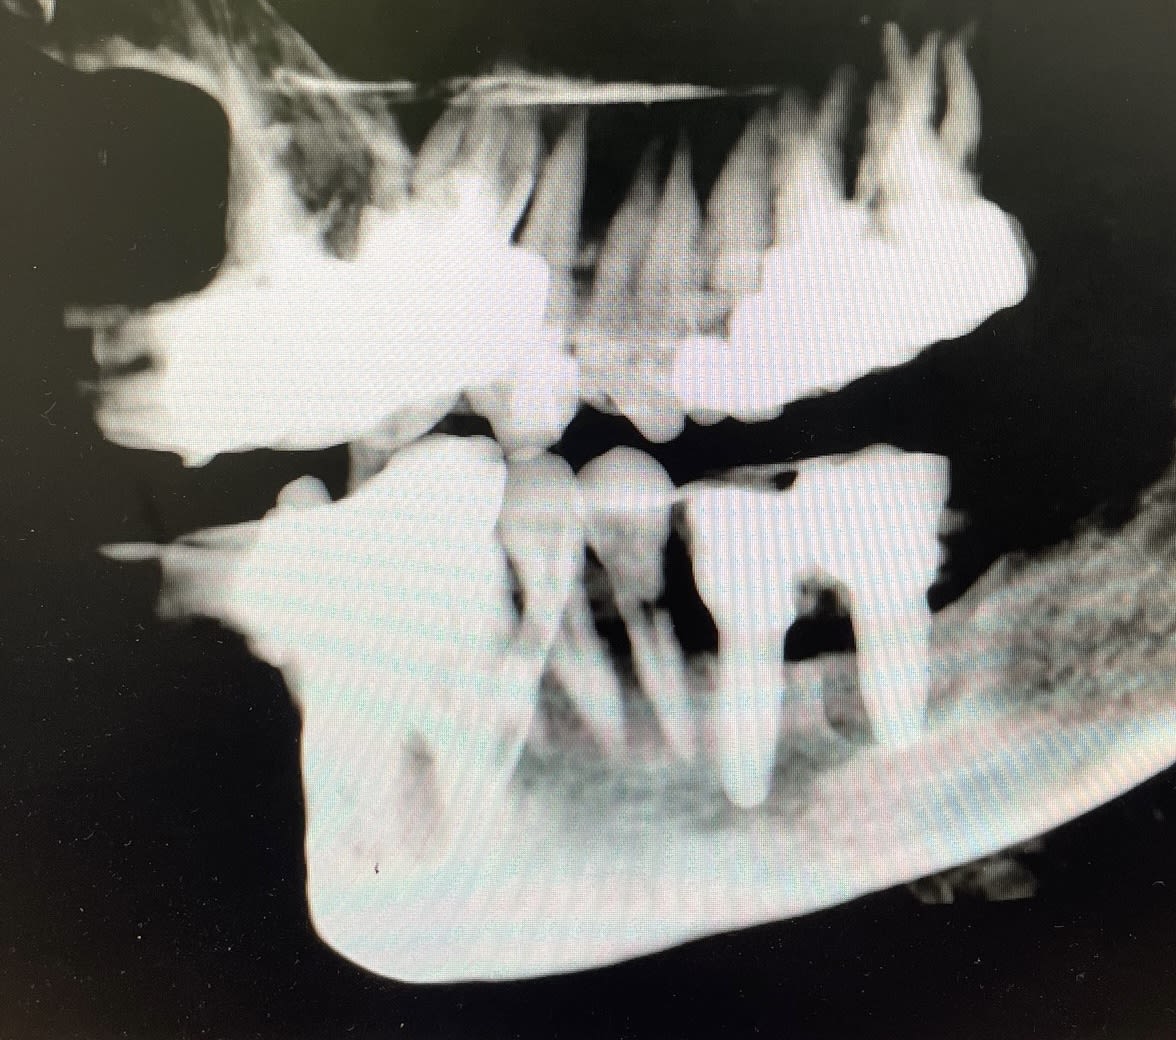

> Patiente motivée, en première approche je m'orienterai plutôt vers une

> stabilisation, contention en visant une survie à 5 /10 ans...

> Pas simple mais à réfléchir, des implants de suite n'auront pas d'avenir à mon

> avis vue les problèmes paros